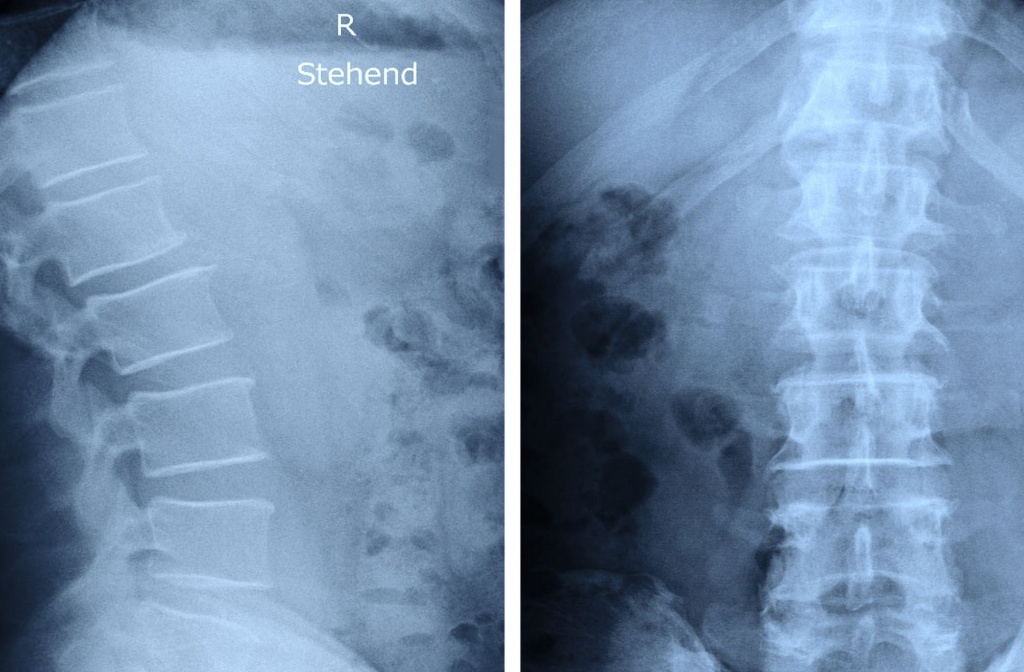

Рентген поперекового відділу хребта – простий і водночас інформативний спосіб побачити, що насправді відбувається зі структурою хребта.

Під час рентгенографії лікар отримує зображення, яке дає змогу виявити:

зміни положення хребців;

наслідки травм і мікротравм;

дегенеративні процеси (остеохондроз, спондилоартроз);

зменшення міжхребцевих проміжків;

викривлення, нестабільність;

ознаки хронічного перевантаження попереку.

Процедура не потребує складної підготовки та займає кілька хвилин. Дослідження проводиться у стандартних проєкціях, що дозволяє отримати чітку картину стану поперекового відділу.